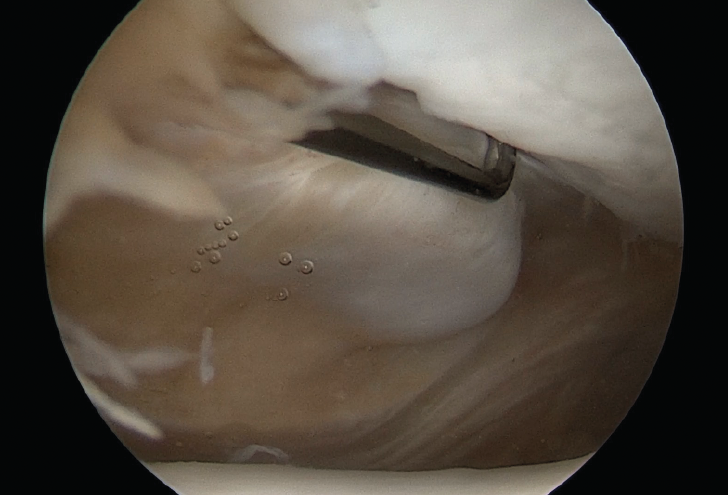

Rodilla izquierda, visión desde el portal anterolateral estándar. Se identifica la carilla articular medial de la rótula en la zona superior derecha de la imagen y la tróclea femoral en la parte inferior. El palpador está situado en el borde medial de la rótula y, a la izquierda del mismo, se aprecia el muñón de la inserción del ligamento patelofemoral medial, avulsionado tras un episodio de luxación lateral traumática de la rótula.